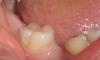

Kast Опубликовано 23 апреля, 2011 Поделиться Опубликовано 23 апреля, 2011 Добрый день!Сходили к 3-м стоматологам, мнения разделились. Один врач сказал, что сбоку развился кариес и нужно срочно лечить, другой - что ничего делать не нужно, это естественное строение зуба, третий предложил сделать герметизацию, но перед этим пройтись пару раз тонким бором. Сверху, на жевательной поверхности в том году делалась герметизация, а на боковых поверхностях, сказали, такого не делается. Это новая технология или врач под видом герметизации сделает обычную пломбу? И на что это больше похоже - кариес или нормальное строение зуба? Требуется ли лечение? Такая же ситуация еще с 3-мя зубами. Ссылка на комментарий

Scrabble Опубликовано 23 апреля, 2011 Поделиться Опубликовано 23 апреля, 2011 Такая фиссура есть на всех шестёрках. У Вашего ребёнка эмаль по фисссуре белая и матовая-это значит, что есть деминерализация. Но если гигиену будете отслеживать(чистить-не филонить, ничего не есть-не пить,кроме воды,после вечерней чистки), всё остановится и реминерализуется. Ещё можно Tooth Mousse дома использовать. И к стоматологу раз в 3 месяца. Ссылка на комментарий

juli63 Опубликовано 23 апреля, 2011 Поделиться Опубликовано 23 апреля, 2011 Требуется ли лечение? тут фото одного мало, чтобы сказать со 100% уверенностью. у меня такое ощущение, что на щечной поверхности в фиссуре уже есть дефект эмали.честно, я бы полечила,если при зондировании это подтвердится. а проблему с белесоватой и матовой эмалью можно решить глубоким фторированием и диетой конечно. наличие современных зубных паст часто усугубляет течение фиссурного кариеса у детей(но это не значит , что зубы чистить не нужно), т.к. эмаль сверху минерализуется, а под ней кариес(если на тот момент он там уже был) цветет и пахнет. сейчас это вижу у каждого 2-го ребенка. и делается герметизация на боковых поверхностях, если там есть проблема. нередко про это просто забывают. Ссылка на комментарий

Kast Опубликовано 25 апреля, 2011 Автор Поделиться Опубликовано 25 апреля, 2011 тут фото одного мало, чтобы сказать со 100% уверенностью. у меня такое ощущение, что на щечной поверхности в фиссуре уже есть дефект эмали.честно, я бы полечила,если при зондировании это подтвердится. а проблему с белесоватой и матовой эмалью можно решить глубоким фторированием и диетой конечно. наличие современных зубных паст часто усугубляет течение фиссурного кариеса у детей(но это не значит , что зубы чистить не нужно), т.к. эмаль сверху минерализуется, а под ней кариес(если на тот момент он там уже был) цветет и пахнет. сейчас это вижу у каждого 2-го ребенка. и делается герметизация на боковых поверхностях, если там есть проблема. нередко про это просто забывают.Да, там есть маленькое углубление, на фото плохо получилось... Врач смотрел с увеличением на компьютере и предложил сверлить. Качество герметизации от цены как-то зависит? В одной клинике нам сделали герметизацию за 3000 руб за 1 зуб - 1500 чистка зуба водной струей и 1500 сама герметизация, а в другой предлагают за 1500 все вместе. Мы сделали обычную гигиеническую чистку зуба неделю назад и врач сказала, что этого достаточно, больше чистить не будет. Ссылка на комментарий